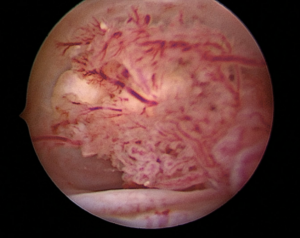

Operative hysteroscopy was conducted for diagnosis. This inpatient procedure required sedation. A vaginoscopic approach using a 30° optic lens from a Bettocchi set was employed and during the procedure, a 2 cm friable polypoid cervical lesion was identified and excised using a 5Fr grasper (See image 1 and 2). Histopathological examination indicated that the tumor comprised papillary excrescences lined by mucosecretory epithelium, supported by dense fibrous stroma with spindle-shaped and stellate fibroblasts. Immunohistochemistry for myogenin and desmin was negative.

Image 1

The macroscopic appearance of mullerian papilloma can easily be mistaken for malignant tumors, particularly vaginal rhabdomyosarcoma, due to its vascularized papillae that may resemble atypical vessels. Treatment involves excising the lesion.